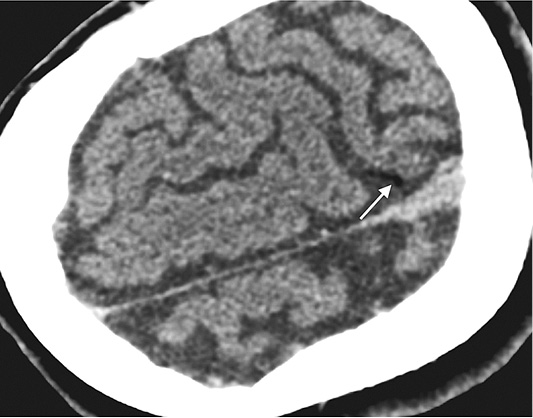

Immediate head CT was performed suspecting neurological pathology. Small air foci were found in peripheral area of left parietal lobe – a clear sign of air embolism (Figure 3). Patient was treated with 100% oxygen.

The next day after the lung biopsy procedure patient felt well, without any neurological disfunction.